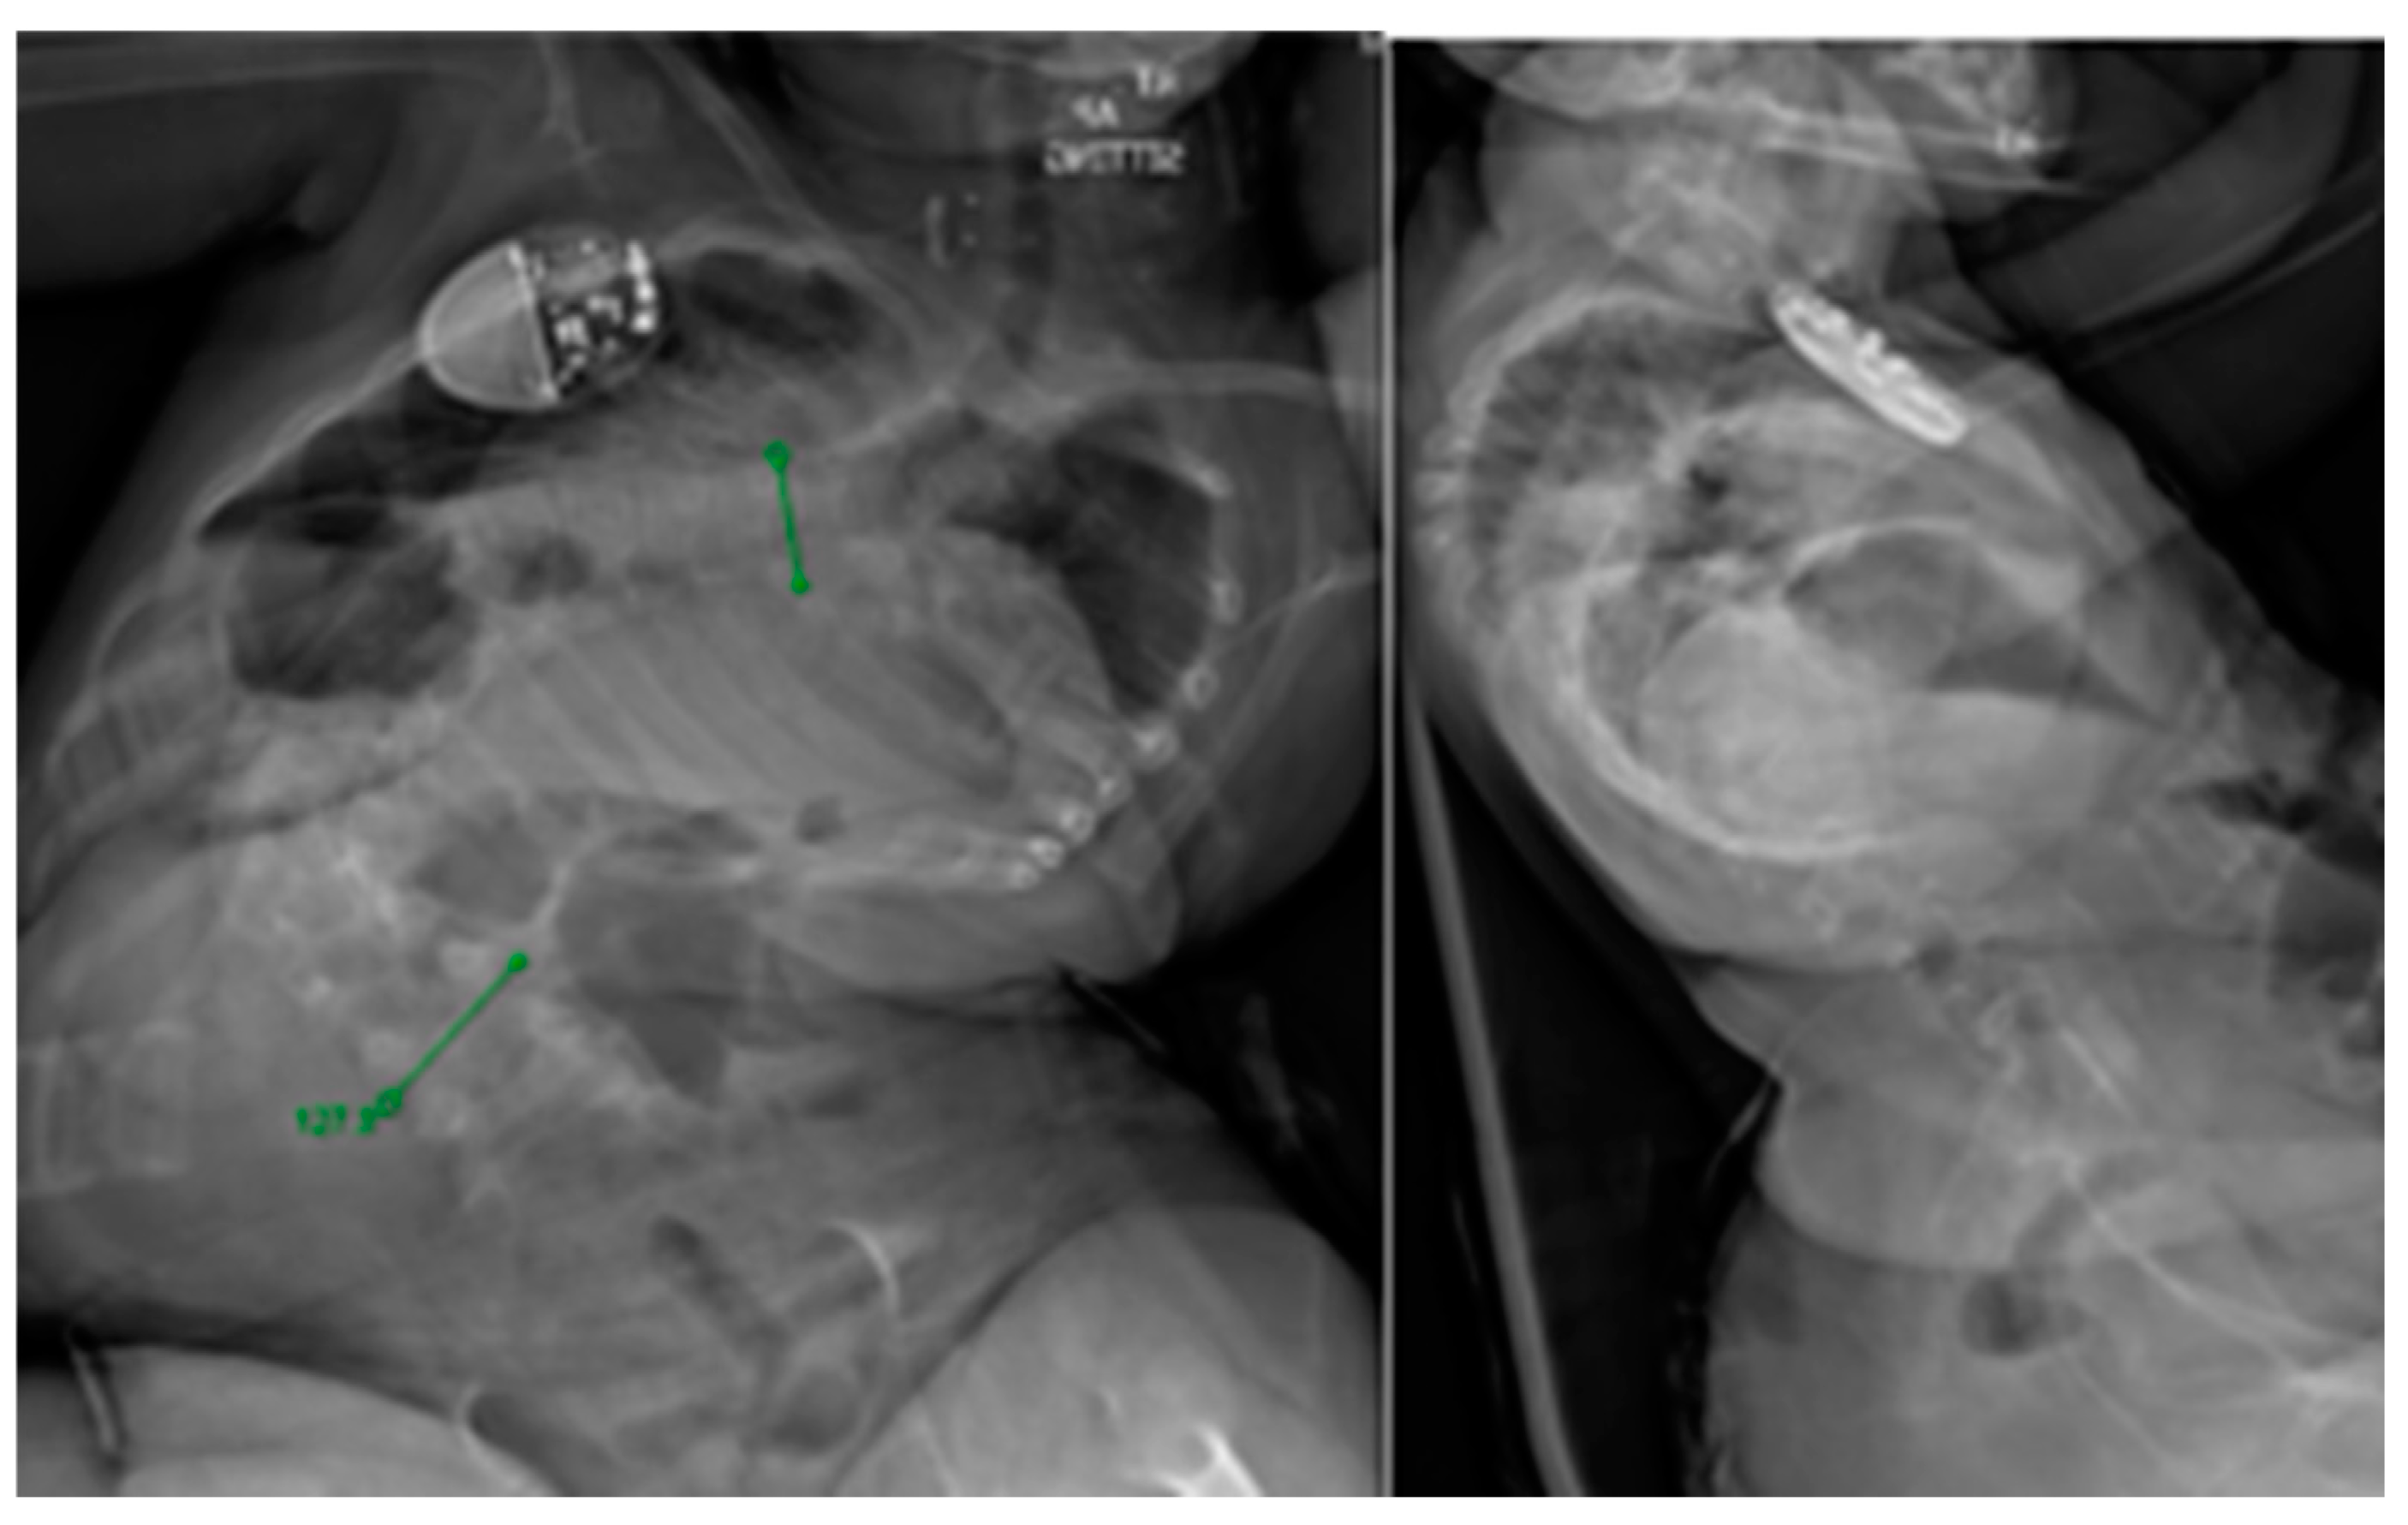

Originally described by Takaso in 1998, MCGRs were developed to address the complications that accompanied TGR lengthenings [38]. After initial implantation, patients are lengthened at short-term intervals in the clinic setting using an external remote control (ERC), eliminating the need for open lengthenings. MCGRs were shown to have similar treatment outcomes with respect to deformity correction and thoracic height, however, the device does have a notable complication profile of its own and requires careful patient selection for optimal use [39]. Various complications have been reported with MCGRs including implant or ERC malfunction and implant breakage or loosening with up to 33% revision rates [40,41]. Recently, concerns over metallosis have been brought forth with histologic changes of phagocytic cells seen in patients undergoing rod exchange with no long-term implications understood at this point [42]. Concerns remain over neurotoxic implications of increased serum titanium as it does cross the blood–brain barrier. Recent studies have suggested rates of unplanned return to the operating room within two years of implantation as high as 40% [43]. For these reasons, the device was suspended in certain countries. Only recently in February 2024 has the system been re-instated in the United Kingdom. Despite its imperfect execution, the implant is widely used. Careful patient selection is necessary when considering MCGRs. Per FDA and manufacturer guidelines, MCGRs are to be implanted only in skeletally immature patients less than 10 years of age with severe progressive spinal deformities associated with or at risk of thoracic insufficiency syndrome (TIS). A clinical example is shown pre-operatively in Figure 1 and post-operatively in Figure 2. MCGRs are inappropriate for patients with insufficient spinal height, inadequate skin and soft tissue cover, a stiff spinal curve, a sagittal curve apex above T3, hyperkyphosis, or patients requiring repetitive MRI [44]. Caution should be exercised in patients with increased soft tissue envelopes and BMI over 25, for example, those with Prader–Willi, which could preclude the transmission of magnetic impulses. Per manufacturer instructions for use, each MCGR unit should be implanted for no longer than 2 years. Further safety information and instructions for proper use are available on the manufacturer’s website and should be carefully studied by implanting surgeons.

Figure 1. Preoperative sitting PA and lateral views of a 5-year-old female with cerebral palsy and associated neuromuscular scoliosis.